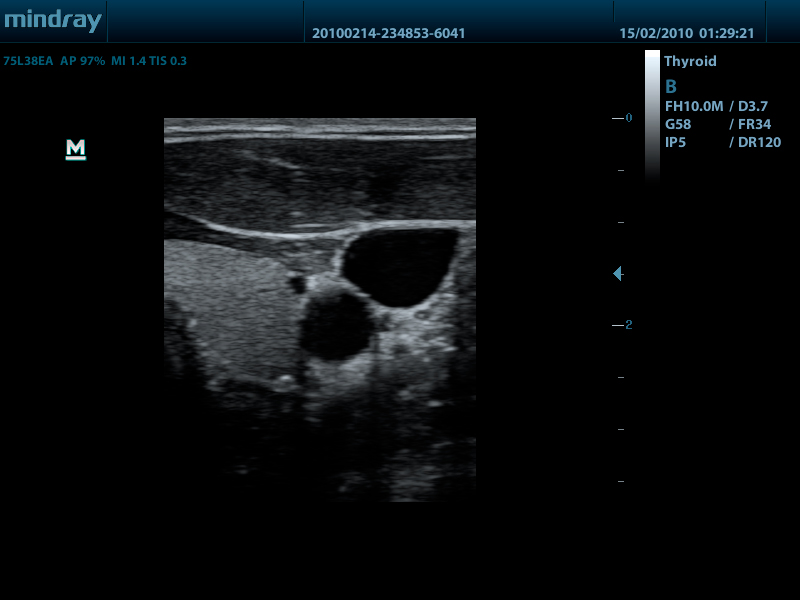

- Широкий выбор мультичастотных датчиков от 2,0 до 14,0 МГц

- Линейный датчик 75L38EA, 3.3 - 13.0 МГц, апертура 38 мм